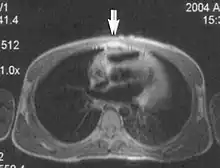

Flow

Flow can manifest as either an altered intravascular signal (flow enhancement or flow-related signal loss), or as flow-related artifacts (ghost images or spatial misregistration). Flow enhancement, also known as inflow effect, is caused by fully magnetised protons entering the imaged slice while the stationary protons have not fully regained their magnetization.[1] The fully magnetized protons yield a high signal in comparison with the rest of the surroundings. High velocity flow causes the protons entering the image to be removed from it by the time the 180-degree pulse is administered. The effect is that these protons do not contribute to the echo and are registered as a signal void or flow-related signal loss (Fig. 2).[1] Spatial misregistration manifests as displacement of an intravascular signal owing to position encoding of a voxel in the phase direction preceding frequency encoding by time TE/2.The intensity of the artifact is dependent on the signal intensity from the vessel, and is less apparent with increased TE.[1]